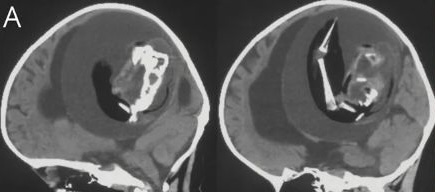

綜合外媒報導,上海復旦大學華山醫院神經科醫生李宗澤是負責治療女嬰的主治醫生,他將該研究發表在美國神經學學會的期刊《神經學》中。李宗澤醫生表示,該名1歲女嬰被發現有動作發展遲緩的情況,且還患有腦積水,因而導致她的頭部變大、嚴重嗜睡和癲癇。

醫療團隊經檢查後發現女嬰的腦內竟然有一個約10公分的胎兒,且從照片中可見脊椎、上肢、骨骼似乎都已長出來了,不過未發育完整,因此研判是女嬰的雙胞胎姊妹。而這種胎兒留存在另一名胎兒體內的情況是一種發育異常,稱之為「胎中胎」(Fetus-in-fetu)。

目前醫療團隊已將女嬰腦中的胎兒取出,但未知後續會否對孩子的健康狀況造成其他影響。根據醫學文獻上的記錄,這種病例非常罕見,目前僅不到200例,且出現在顱內的只有18例,據了解,大約每50萬個新生兒中就會有一例胎中胎。